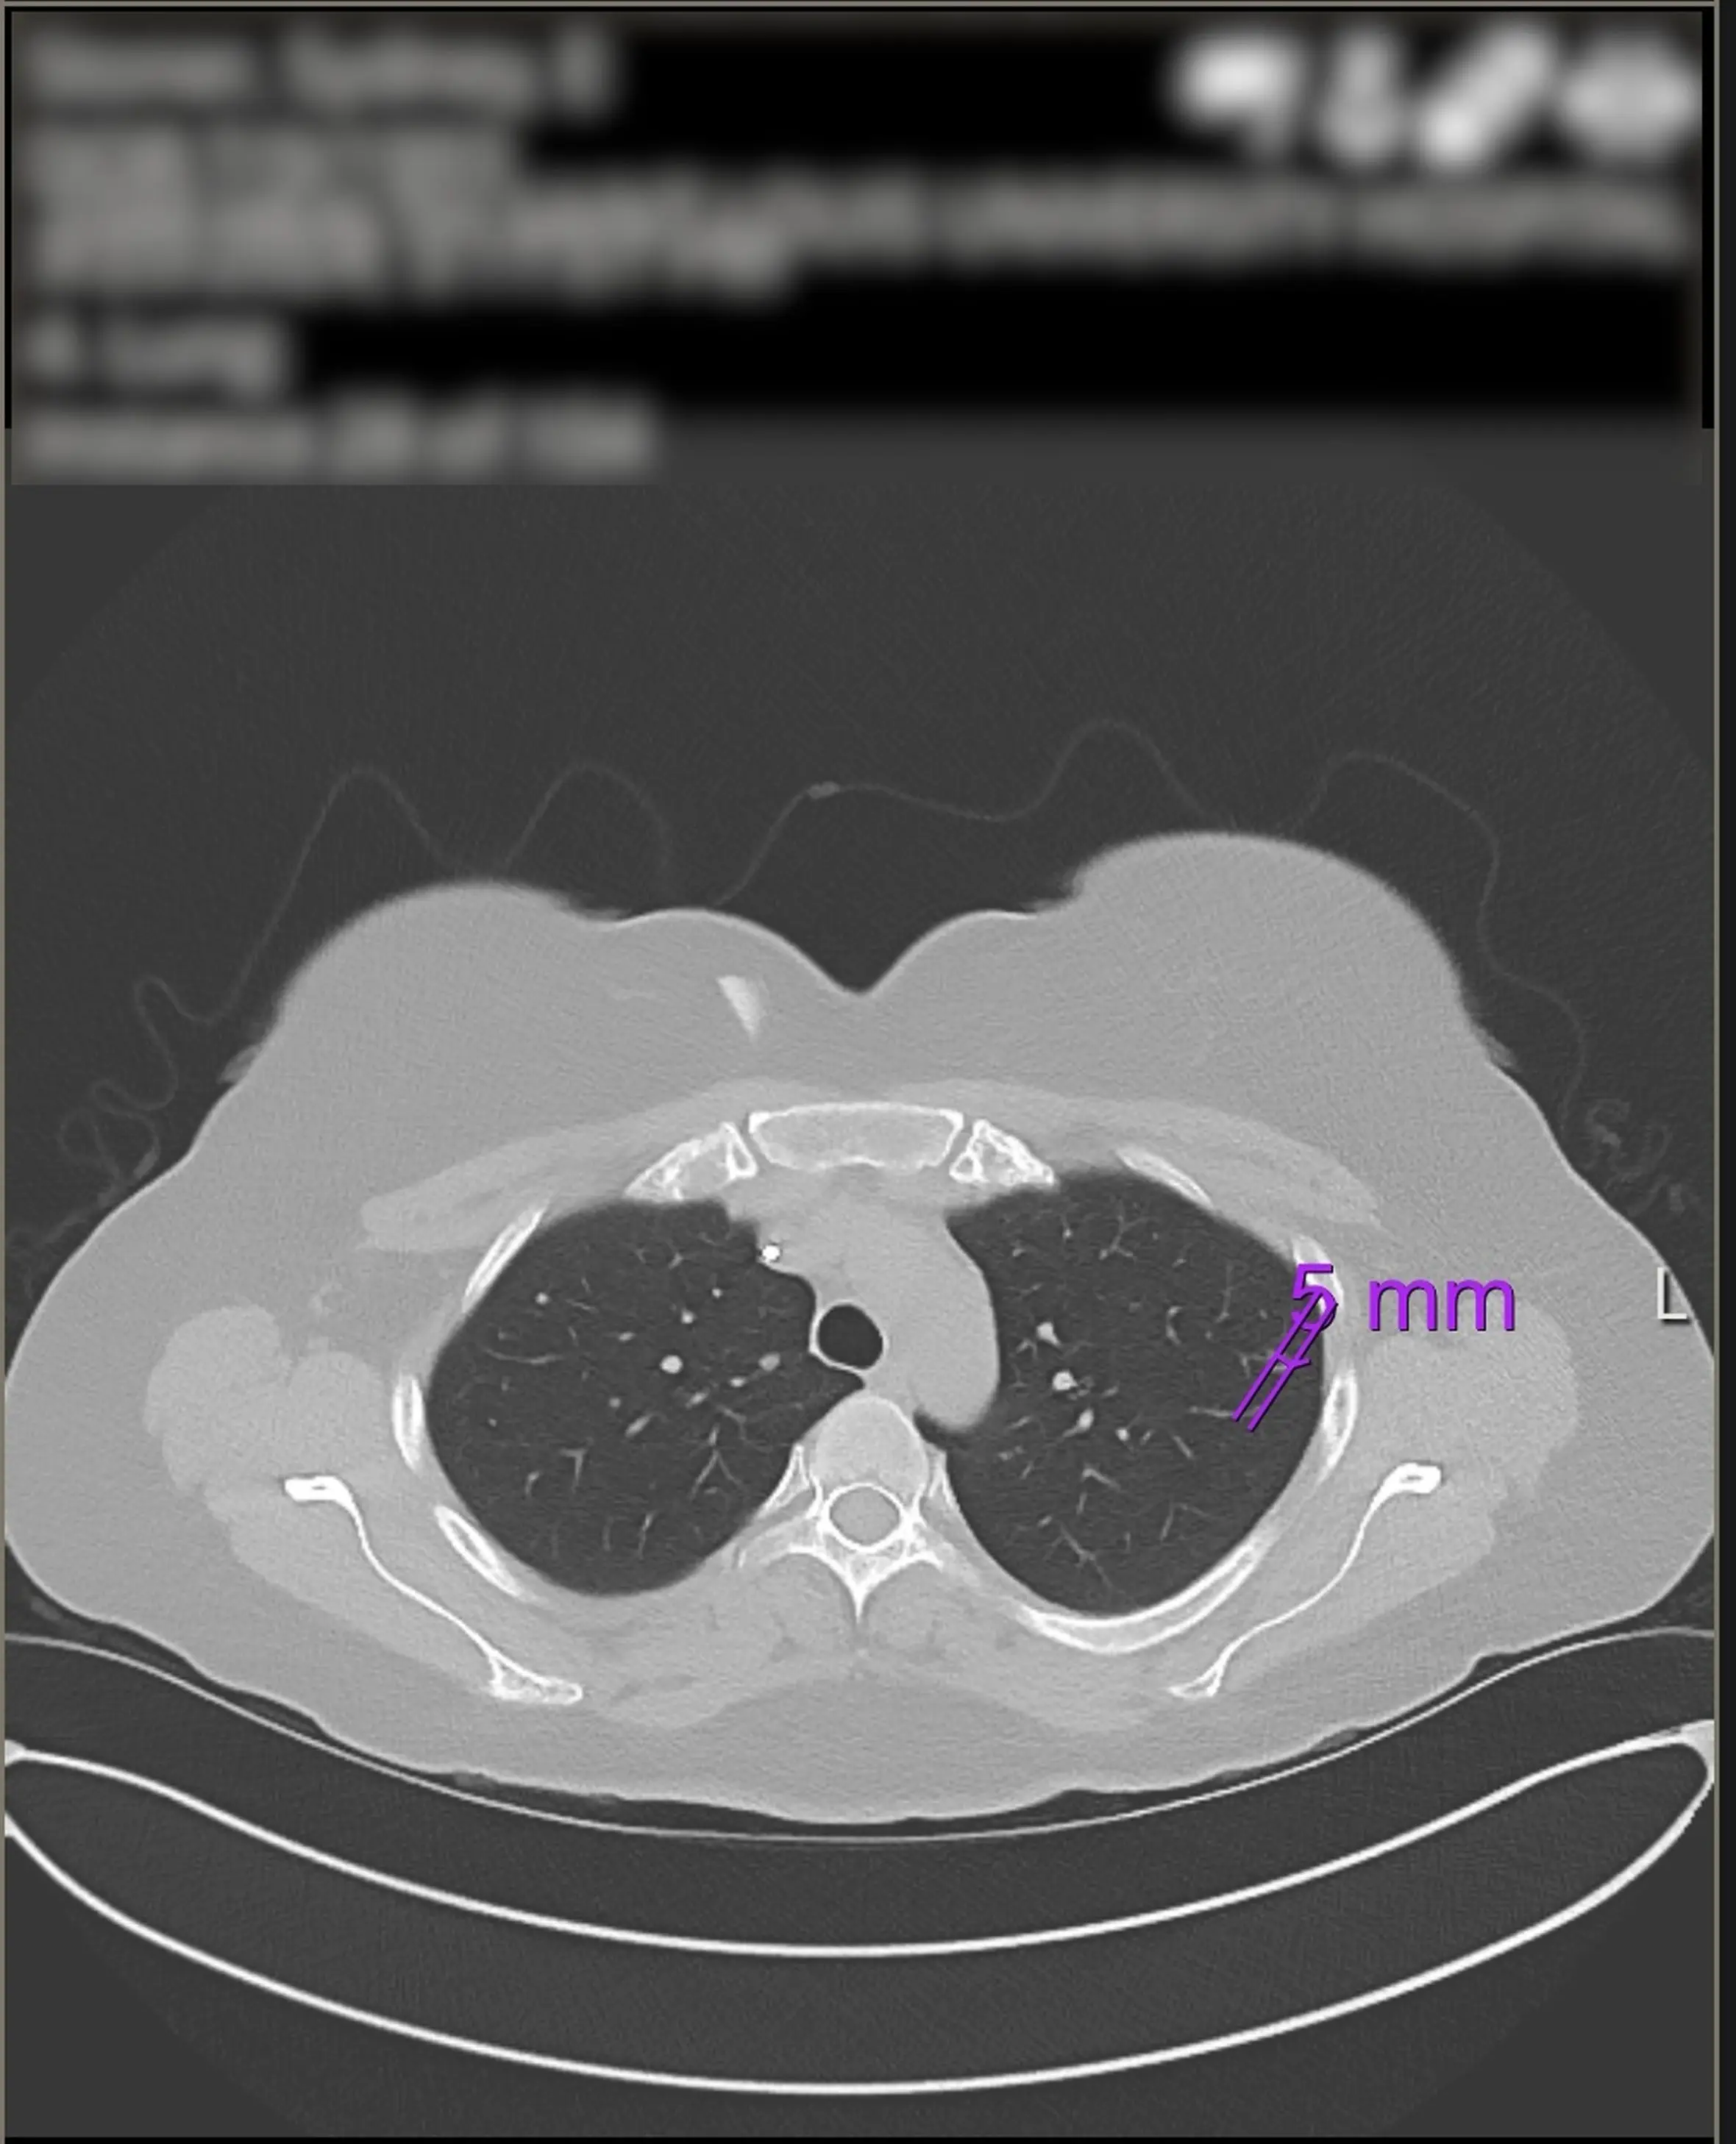

Having once wondered if her symptoms were related to something like a food intolerance, food poisoning or even travel sickness, Sydney was diagnosed with stage four bowel cancer which had spread to her liver and lungs.

The cancer from her colon was removed in September 2020 and from her liver in 2023 while she is still undergoing chemotherapy for her lungs.